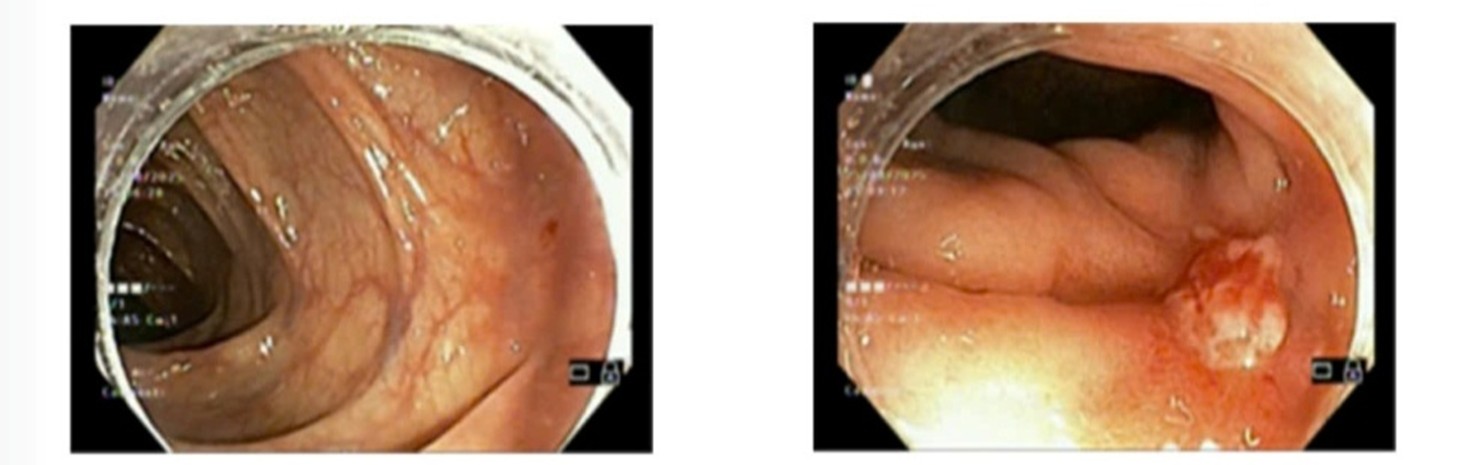

- Nội soi đại trực tràng: cách rìa hậu môn 8cm có vùng niêm mạc sùi ~1cm, niêm mạc xung quanh co kéo (giảm kích thước)

Hình 1. Hình ảnh khối u trực tràng sau điều trị